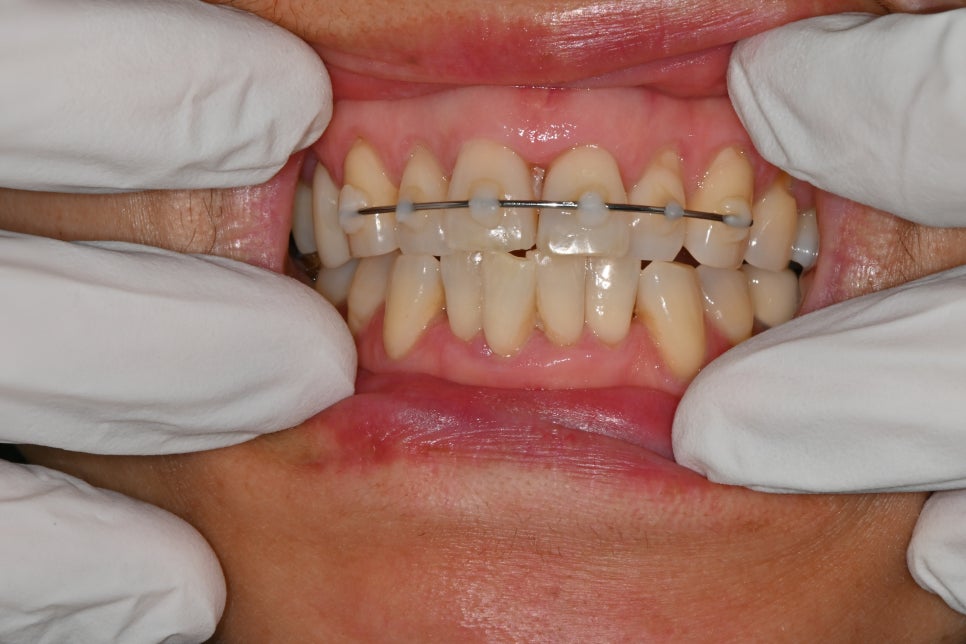

Alveolar bone fracture and front tooth stabilization device

- Alveolar bone fracture & front tooth stabilization

When a front tooth is pushed backward or becomes loose due to impact,

it must be returned to its proper position and stabilized for a certain period.

In this case as well,

were performed.

This helps the tooth reattach stably to the bone.

If it is not stabilized or if treatment is delayed, the tooth may move further and the risk of nerve necrosis increases.